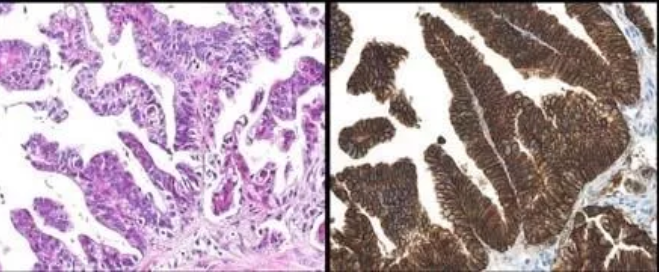

胃镜:进镜40cm见息肉样病变延及贲门及胃底、胃体,胃腔狭窄,尚能通过镜身,胃体中部近半周弥漫性粘膜破坏区,咬检病理(胃底)中分化腺癌,(贲门)粘膜急慢性炎症,腺体重度不典型增生,于炎性渗出及坏死组织中见异型细胞巢;HER2过表达,IHC 3+。肿标:CA199 742U/ml;CEA 78U/ml。胸腹盆CT:贲门胃底胃壁及胃体上部胃壁不规则增厚;下纵膈贲门周围肝胃韧带区及腹膜后多发肿大淋巴结;腹盆腔少量积液。

病理科:中分化腺癌明确,HER2扩增明确。

1.HER2阳性率

在胃癌中,HER2阳性率约10%~20%。两项中国大型多中心研究显示,中国胃癌HER2阳性率为12%~13%。胃癌HER2检出率受到肿瘤部位、病理类型、分化程度等因素的影响。从发病部位来讲,胃-食道接合部的胃癌HER2阳性率高,可达30%;从病理类型来看,肠型胃癌的HER2阳性率高;从分化程度来看,高分化、中分化型胃癌比低分化型的胃癌HER2阳性率高。本例贲门胃底腺癌,HER2阳性,提示我们HER2常规检测的重要性,特别是对胃食道接合部的胃癌,更要重视HER2的检测。